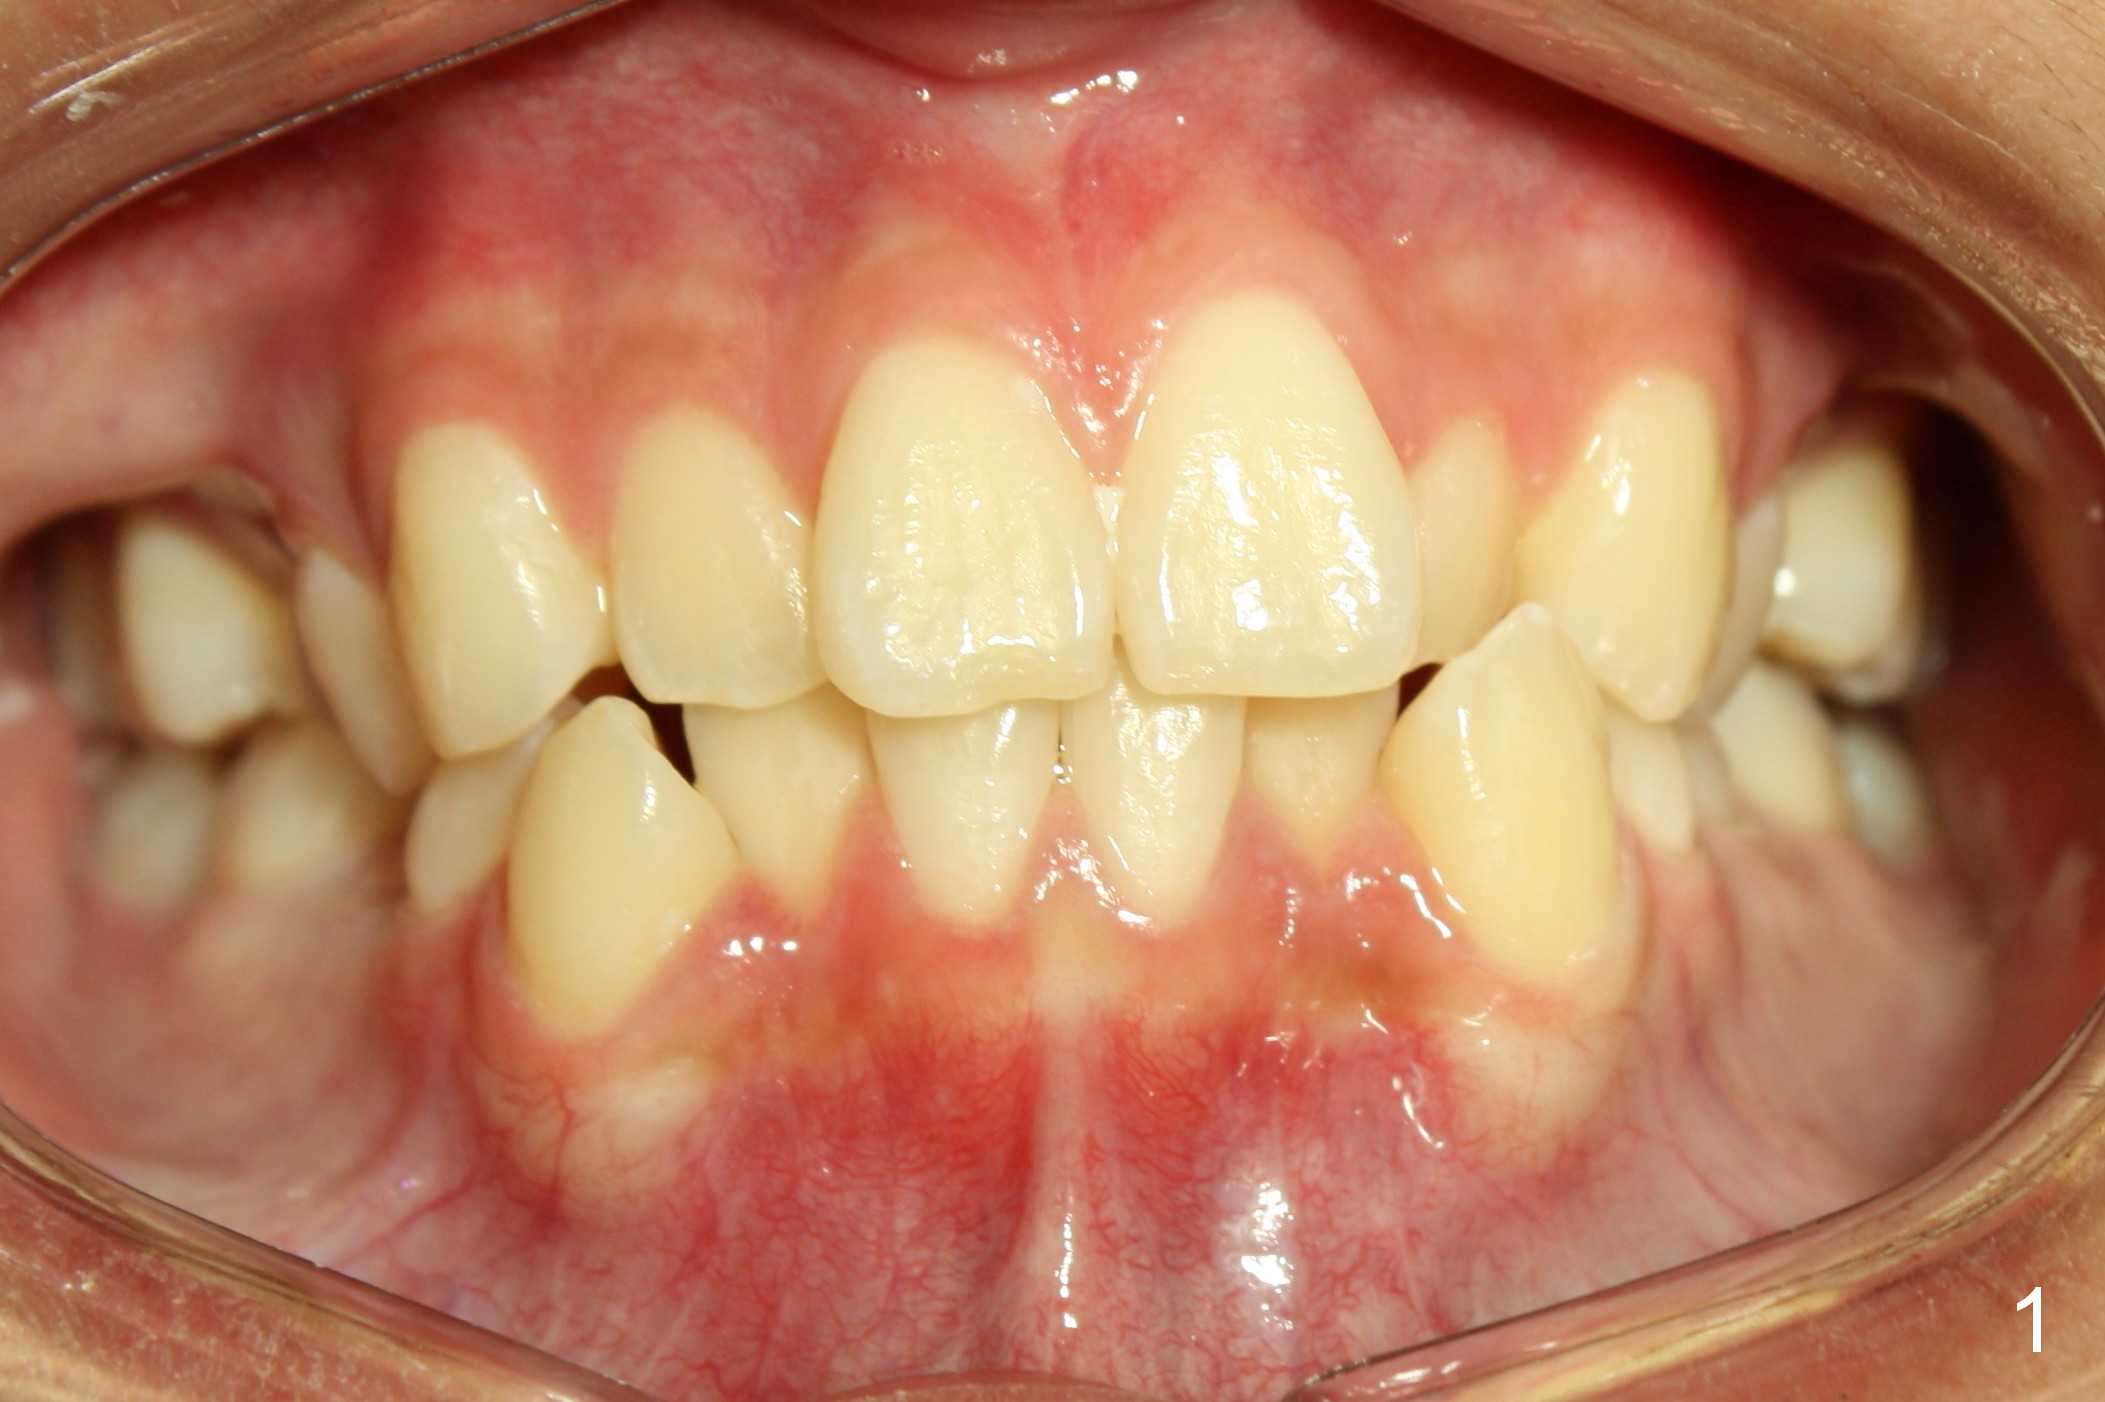

Lighting should be double checked (Fig.1,2).